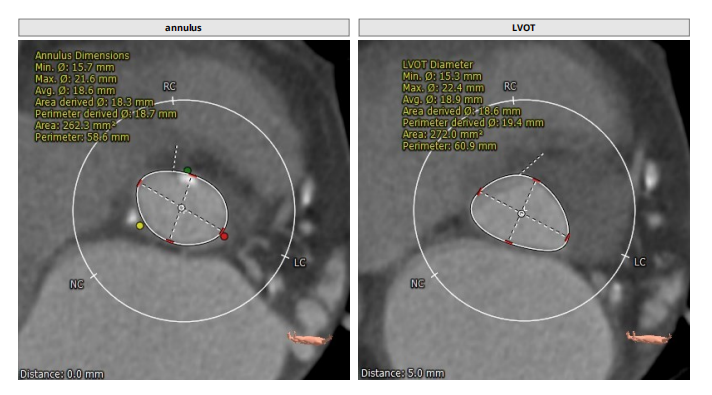

术前CT分析

三叶瓣,轻中度钙化,右无疑似融合,左冠开口高度低,右冠开口高度不高,法式窦结构不大,左室大小可,升主动脉未见明显扩张。小窦,小瓣环,准备瓣膜型号L23。